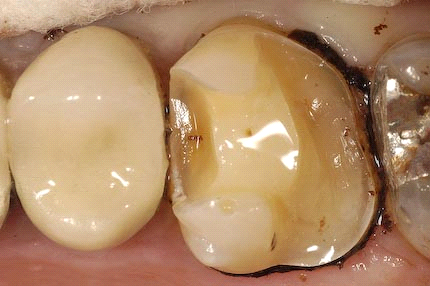

就诊 主诉:右下后牙食物嵌塞五年余 现病史:五年来

图片尺寸920x690